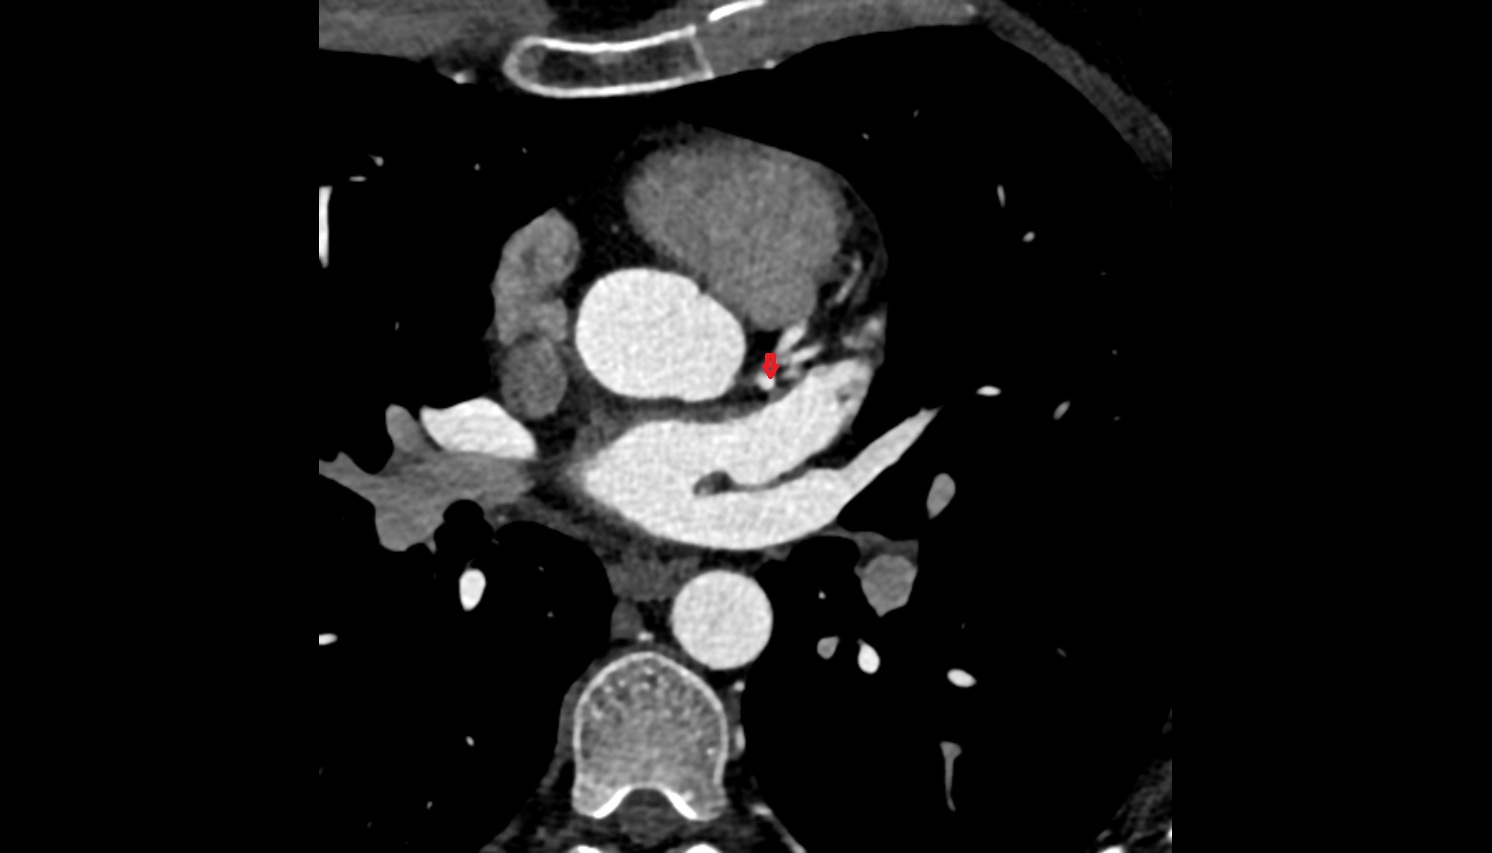

- Left anterior descending artery (LAD)

- Circumflex artery (LCx)

- Left main coronary artery (LMCA)

- Right coronary artery (RCA)